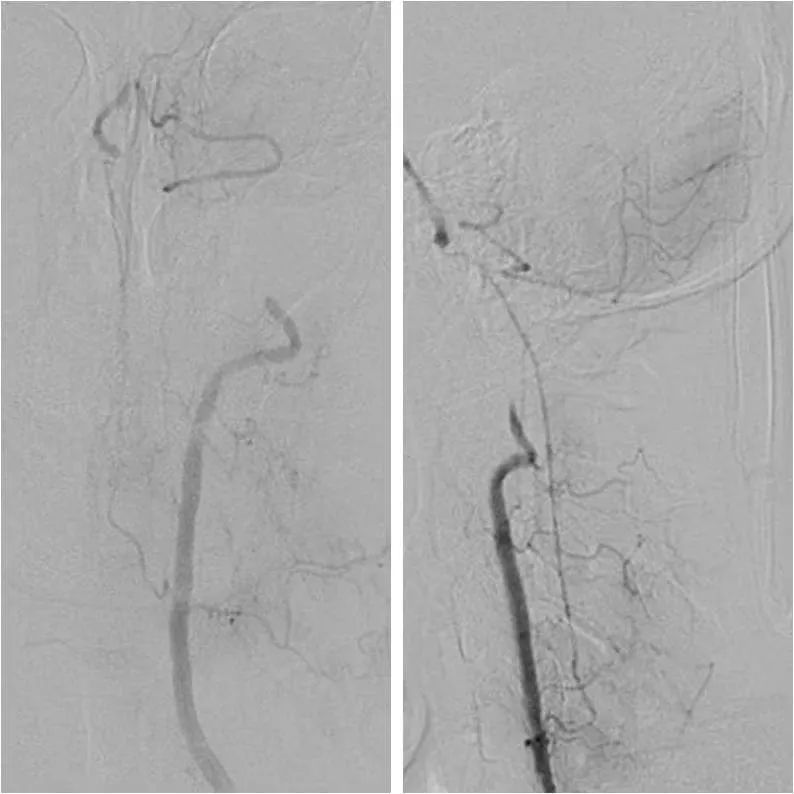

头部CTA+CTP:右椎动脉V4段长段重度狭窄,左椎动脉V3段闭塞,基底动脉近端见开窗(图5);后循环分布区低灌注(图6)。

图5

高分辨磁共振:左椎动脉闭塞,管腔可见高信号血栓,负荷量较大。右椎动脉管壁增厚,管腔狭窄(图7)。

图7